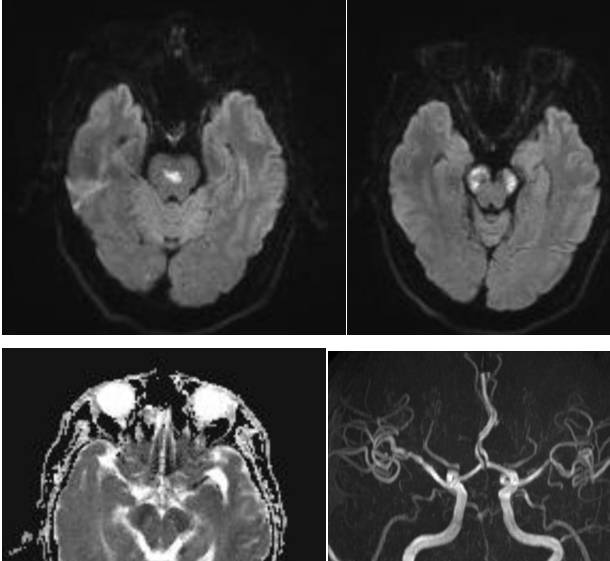

女,60岁,眶后头痛2月,视力下降伴复视4天。

答案:颈内动脉-海绵窦瘘。狭义的颈内动脉海绵窦瘘(CCF)通常指的是颈内动脉海绵窦段的动脉壁或其分支发生破裂,以致与海绵窦之间形成异常的动静脉交通,而广义的CCF还包括海绵窦的硬脑膜动静脉瘘。Barrow等在1985提出了广义的CCF分型,分别为:A型,颈内动脉直接与海绵窦相交通;B型,颈内动脉分支与海绵窦相交通;C型颈外动脉分支与海绵窦相交通;D型即B+C,颈内和颈外动脉都通过其脑膜支与海绵窦相通,常有双侧同时供血。临床工作中,由于治疗理念和方法上存在区别,目前通常将BarrowA型单列为CCF,又称直接型颈动脉海绵窦瘘(狭义CCF),而B、C和D型统称为海绵窦硬脑膜动静脉瘘。CCF可分为外伤性和自发性。外伤性CCF较为常见,通常见于交通事故中伴有颅底骨折的外伤患者,颞骨和蝶骨的骨折碎片刺破海绵窦段颈内动脉壁,骨折片吸收后而出现CCF。因此CCF的症状通常发生于外伤后数周或数月。

CCF的症状与瘘口的流量以及引流方式有关。根据典型的病史及体征,CCF的临床诊断通常并无疑问,CTA/MRA有助于进一步明确诊断和鉴别诊断。DSA则是诊断的金标准,也为治疗提供了详尽的血管结构学和血流动力学信息。